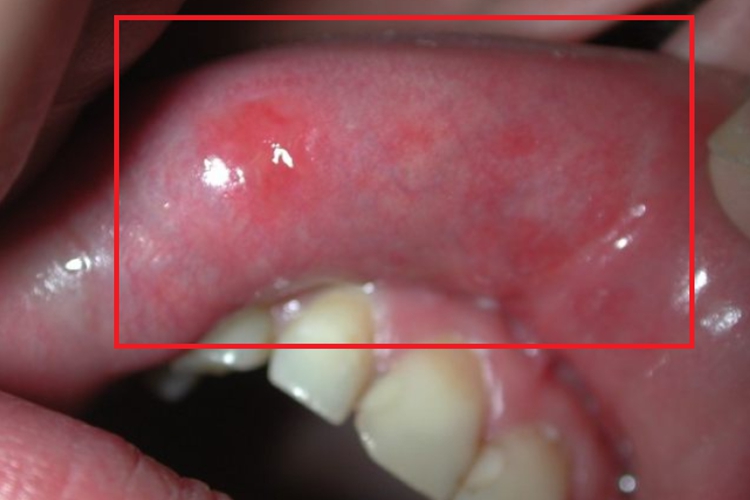

颌面部梅毒的皮肤损害可发生在唇内侧,临床可表现为形状不规则的红斑,大小、数量不等,分布无具体规则,边界模糊,红斑表面光滑且红肿,质地稍硬。